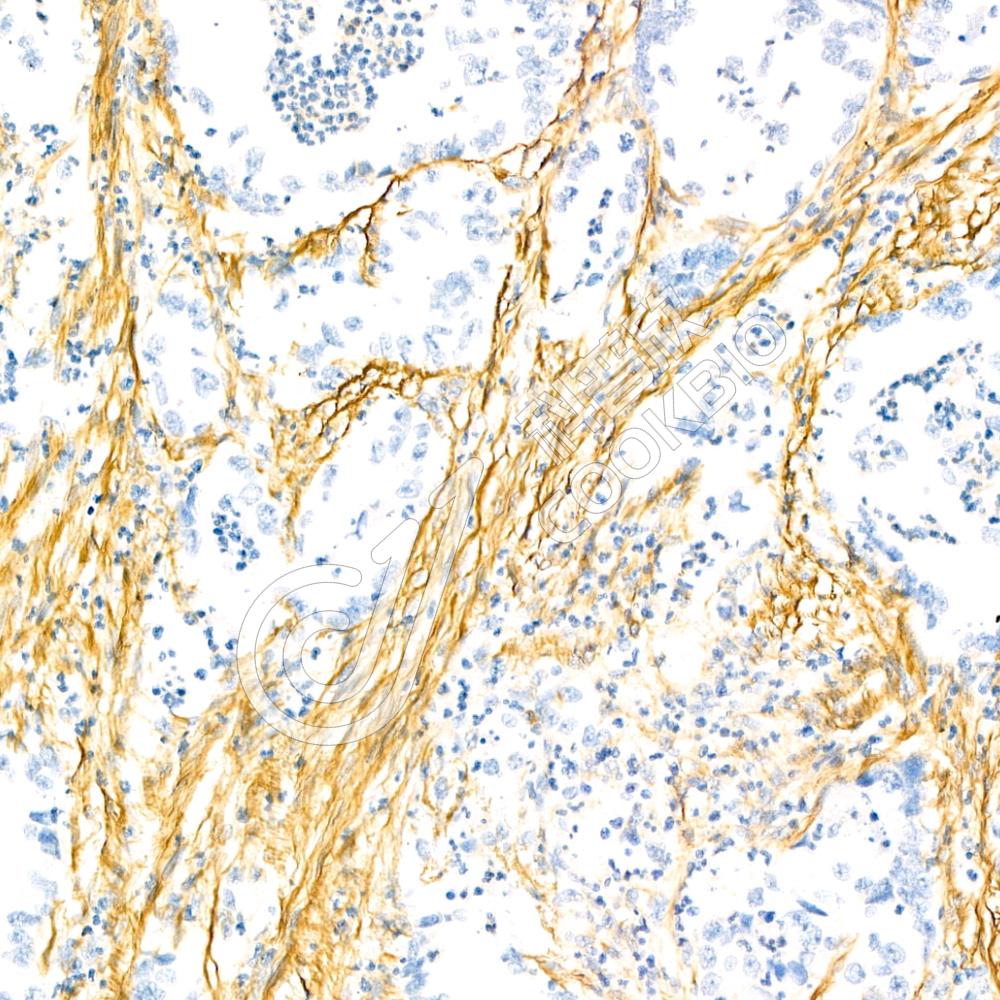

IHC检测Fibronectin蛋白(货号 K236273).

样品: 人食管癌, 4%多聚甲醛 (货号KSG1101) 固定12-24小时.

抗原修复: 蛋白酶K(KSG1234)(200微克/毫升)在55℃条件下用于抗原修复20分钟.

—抗: 1: 300稀释, 4℃ 孵育过夜.

二抗: S-vision免疫组化多聚二抗(山羊抗小鼠), 即用型(货号KB3903), 室温孵育20分钟.

样品: 人胃癌, 4%多聚甲醛 (货号KSG1101) 固定12-24小时.